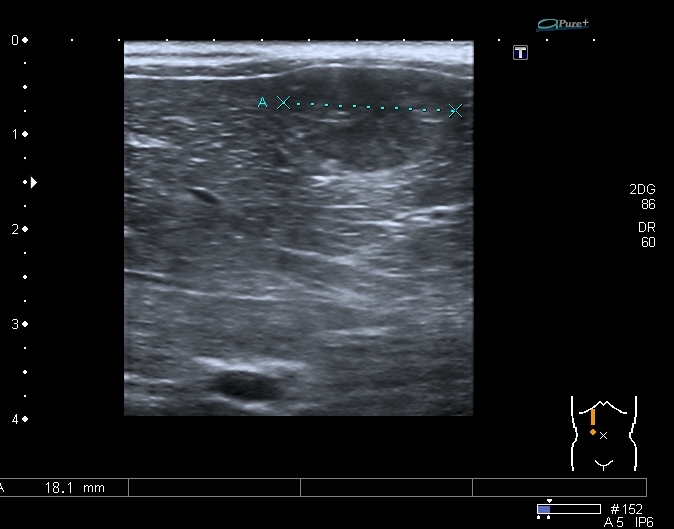

Добавлю ещё сканы, что бы активизировать общество ( показался рояль из кустов

Добавляю источник изменений в легких, печени и забрюшинном пространстве

Всё левое подреберье было выполнено опухолевым конгломератом, источником его я предположил левую почку, хотя разобраться , где почка, селезёнка, а тем более надпочечник я не смог.

По сложившейся тактике при обнаружении опухолевых образований мы не занимаемся морфологической верификацией, а отправляем ребёнка в головное учреждение, наверное это правильно - в лечении детских опухолей иногда бывают важны даже часы. Тем не менее , по УЗИ картине больше данных за нефробластому - есть остатки деформированной собирательной системы в области нижнего полюся образования, там же - немного ткани, похожей на нормальную почечную.